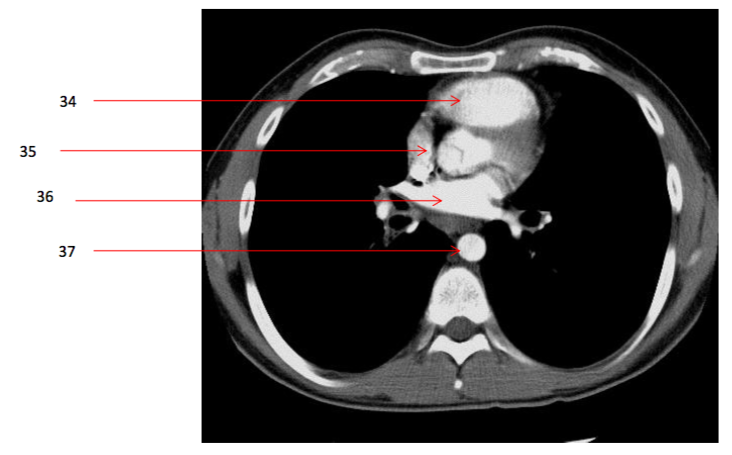

Number 36?

Lt atrium

Number 21?

SVC

Number 22?

Azygos vein

Number 20?

Ascending aorta